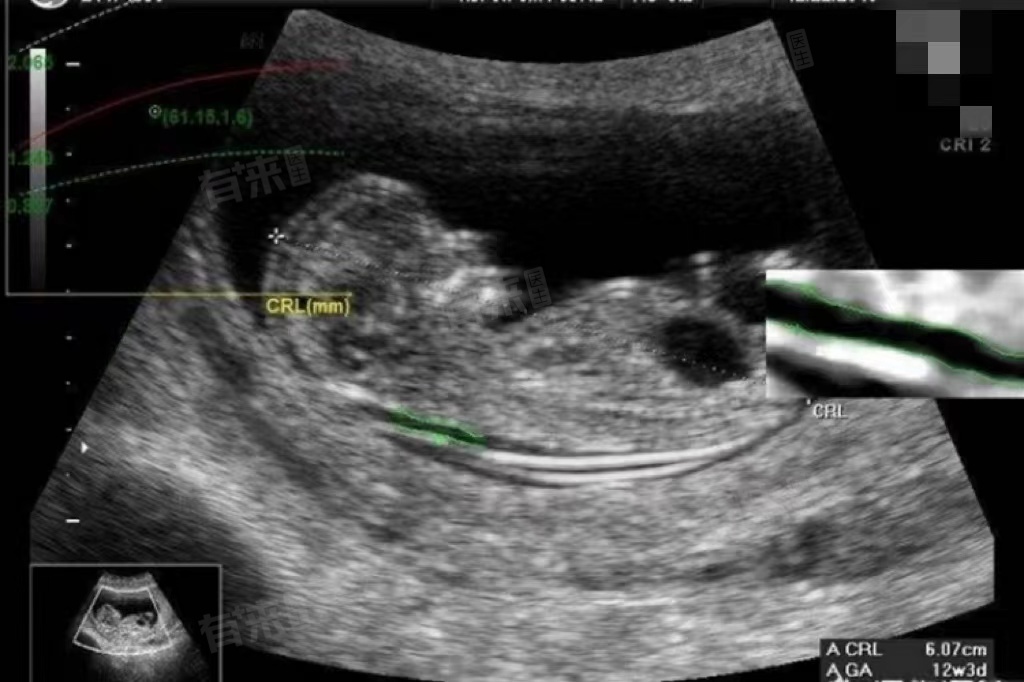

- NT检查的最佳时间是在怀孕11周至13周+6天之间进行,这是因为在这个时间段内,胎儿颈项透明层的厚度可以通过B超清晰地观察到,且测量结果较为准确。如果检查时间过早或过晚,都可能会影响测量结果的准确性。

- 正常情况下,NT值应小于3.0mm,当NT值超过这一标准时,说明胎儿颈项透明层增厚,可能存在染色体异常或其他结构异常的风险。